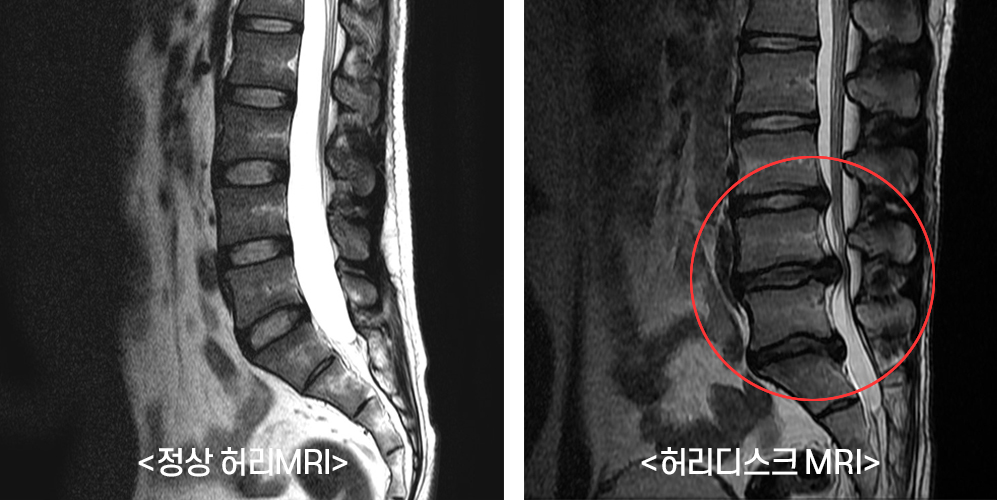

허리디스크는 현대인에게 매우 흔한 문제이며, 이를 통해 다양한 증상이 나타날 수 있습니다. 허리디스크, 즉 추간판 탈출증은 척추 디스크가 돌출되거나 파열되어 신경을 압박하게 되는 상황을 말합니다. 이로 인해 통증과 불편함이 발생하며, 일상생활에 큰 지장을 줄 수 있습니다.

허리디스크는 다양한 증상을 동반하며, 개인마다 증상의 강도와 양상이 다를 수 있습니다. 일반적으로 허리 통증은 가장 흔하게 나타나는 증상 중 하나입니다.